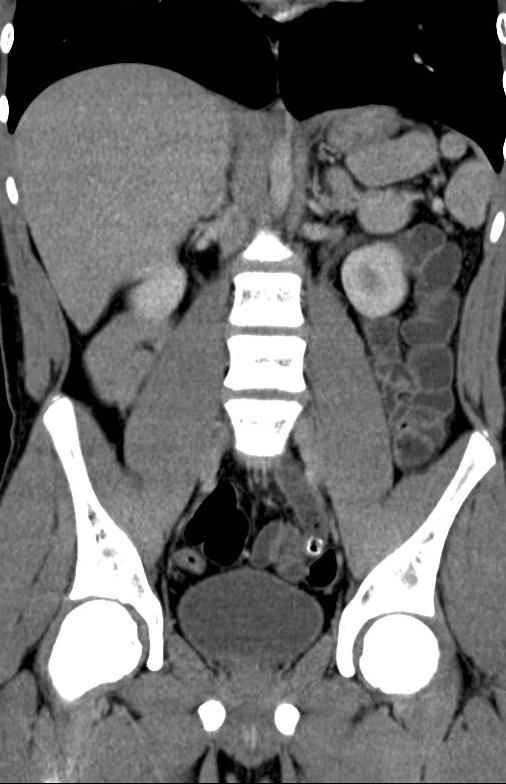

From www.ntvg.nl

Pijn links onder in de buik NTVG Pijn Onder In De Buik Links En Rechts  Bij vrouwen kan pijn in de rechter onderbuik soms ook van de. De locatie van je buikpijn zegt veel over de mogelijk getroffen organen. Pijn in de onderbuik kan rechts gevoeld worden. Pijn in onderin de buik (lage buikpijn) is een veel voorkomende pijn. Hieronder een overzicht van de locaties en de organen. Pijn in de rechter onderbuik kan veroorzaakt. Pijn Onder In De Buik Links En Rechts.

Een jongen met pijn links onder in de buik Nederlands Tijdschrift Pijn Onder In De Buik Links En Rechts  Pijn in de rechter onderbuik kan verschillende oorzaken hebben, van ernstige tot minder ernstige. De oorzaken kunnen uiteenlopen van onschuldig naar levensbedreigend. De minder ernstige oorzaken zijn onder meer: Pijn in de rechter onderbuik kan veroorzaakt worden door gasvorming en dyspepsie of. Pijn rechtsonder in je buik komt meestal van je dikke darm of je blinde darm. De buikpijn kan. Pijn Onder In De Buik Links En Rechts.